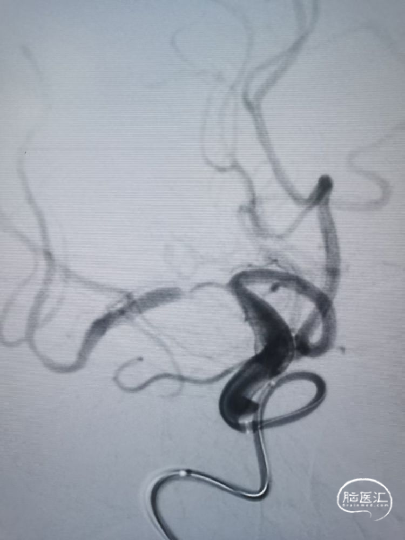

撤出微导管,输送国产快交型1.5mm×10mm球囊,到位困难,调整中间导管越过虹吸弯、床突上段接近狭窄,球囊仍无法通过最狭窄处,撤下换用同轴型Gateway 1.5mm×15mm,顺利通过狭窄。

予缓慢充盈球囊至10atm,透视下观察球囊已充盈饱满,静待20秒,缓慢泄压球囊,造影提示局部管腔毛糙并粗细不均,担心弹性回缩基础上伴夹层形成。

撤出球囊,交换XT-27微导管小心通过狭窄,稳定释放Neuroform EZ 3.5mm×20mm支架。